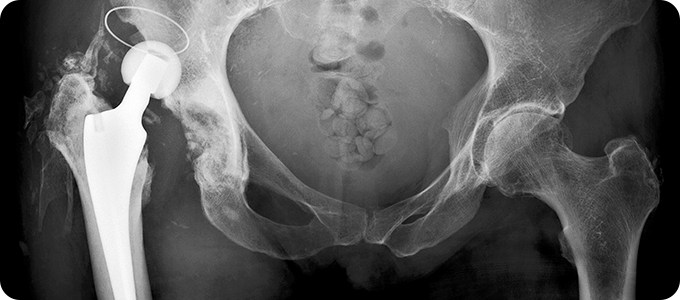

고관절골절

부분치환술 관련 이미지

• 허벅지 뼈와 골반의 연결 부분인 고관절에 금이 가거나 부러지는 것입니다.

골절이 발생하면 환자의 움직임이 제한되어 대부분의 시간을 누워 있게 되므로

욕창, 폐렴, 뇌졸중, 심근 경색, 인지 능력 저하 등의 합병증이 나타날 수 있습니다.

• 대부분 넘어지면서 고관절부의 외측을 직접 부딪히면서 발생합니다.

젊은 연령에서는 추락이나 교통사고 같은 고에너지 외상에 의한 것이 대부분입니다.

노인들은 골다공증으로 인해 가벼운 낙상에 의해서도 뼈가 부러질 수 있습니다.

• 골절 후 즉시 허벅지 바깥쪽과 사타구니에 심한 통증이 있습니다.

다리를 움직일 수 없습니다. 고관절을 움직일 경우 더욱 심한 통증이 나타납니다.

골절된 쪽의 다리가 반대쪽에 비해 짧아지며, 발과 무릎이 바깥쪽으로 돌아가있습니다.